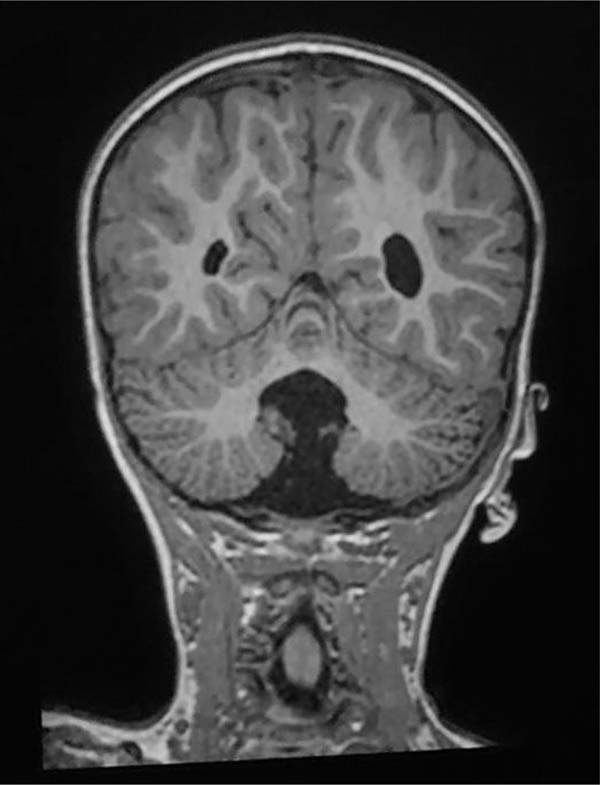

A skull MRI revealed hypoplasia of the cerebellar vermis, dilatation of the fourth ventricle, and communication with the cisterna magna, but no signs of hydrocephalus (►Fig. 2). The scan also showed no skeletal or renal abnormalities.